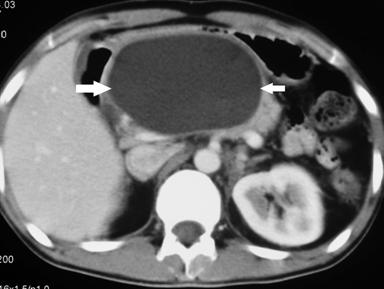

A 32 year old male patient diagnosed as alcohol related acute necrotising pancreatitis (ANP) 2 months ago, now presented with abdominal pain and early satiety. Contrast enhanced computerized tomography (CECT) showed 12 cm walled off pancreatic necrosis (WOPN) (Figure 1). Endoscopic ultrasound (EUS) revealed large WOPN and power doppler revealed vascularity in collection with pulsatile flow suggestive of blood leaking into collection (Figure 2). However, no abnormal vessel or pseudoaneurysm could be identified. CT angiography (CTA) also showed normal major abdominal arteries (Figure 3). Since patient was symptomatic, after informed consent EUS guided transmural drainage was attempted. Now there was no vascularity in collection and procedure was successfully accomplished. A 7 Fr nasocystic drain (NCD) was inserted and it drained purulent material. Patient had marked symptomatic relief but 6 hours later had severe pain and hematemesis with blood coming through NCD also. CTA revealed blood in WOPN but no abnormal bleeding vessel was identified (Figure 4). Digital subtraction angiography (DSA) also did not reveal any abnormal or bleeding vessel. The patient was managed with blood transfusion and NCD was kept patent by intermittent flushing. The bleeding subsided and the effluent from NCD cleared in 48 hours. The NCD was replaced with 10 Fr pigtail stents and CT abdomen done 3 weeks later revealed resolution of WOPN (Figure 5). The patient has been asymptomatic over a follow up period of 13 months.

Figure 1. Large WOPN (arrow). |